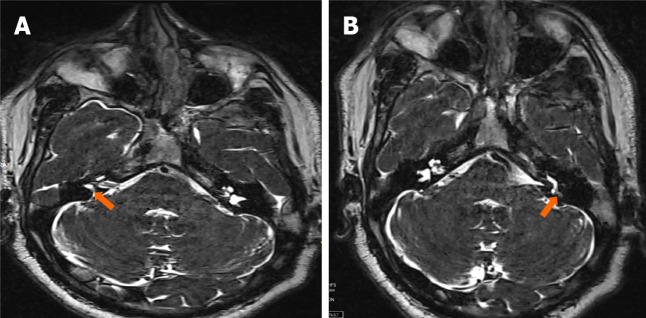

慢性中耳炎(COM)是一种影响中耳和乳突腔的长期炎症,通常导致进行性结构损伤和功能缺陷。放射成像是诊断疾病、评估其严重程度和识别可能的并发症的基础。文献显示颅外、颅内合并症患病率为0.69% ~ 5%,颅内合并症死亡率为26%。虽然磁共振成像在区分软组织异常和检测颅内延伸(如脑膜炎、脑脓肿和乙状窦血栓形成)方面特别有用,但高分辨率计算机断层扫描仍然是评估骨侵蚀、胆脂瘤和乳突受累的首选方式。关键并发症,如听骨链破坏、面神经损伤和迷路瘘管可以通过先进的成像方式精确识别,允许及时有效的手术干预。这篇小型综述强调了放射学在诊断和治疗COM中的重要作用,强调了有助于早期发现和指导治疗决策的关键影像学发现。放射科医生、耳鼻喉科医生和传染病专家之间的合作方法对于改善受影响患者的临床结果至关重要。

Chronic otitis media (COM) is a long-standing inflammatory condition affecting the middle ear and mastoid cavity, often resulting in progressive structural damage and functional deficits. Radiological imaging is fundamental in diagnosing the disease, assessing its severity, and identifying possible complications. The literature indicates that the prevalence rates of extracranial and intracranial complications range from 0.69% to 5%, while the mortality rate for intracranial complications is 26%. While magnetic resonance imaging is particularly useful in distinguishing soft tissue abnormalities and detecting intracranial extensions like meningitis, brain abscess, and sigmoid sinus thrombosis, high-resolution computed tomography remains the preferred modality for evaluating bony erosion, cholesteatoma, and mastoid involvement. Key complications such as ossicular chain destruction, facial nerve damage, and labyrinthine fistulae can be precisely identified using advanced imaging modalities, allowing for timely and effective surgical intervention. This minireview underscores the essential role of radiology in both diagnosing and managing COM, highlighting critical imaging findings that facilitate early detection and inform treatment decisions. A collaborative approach among radiologists, otolaryngologists, and infectious disease specialists is crucial for improving clinical outcomes in affected patients.